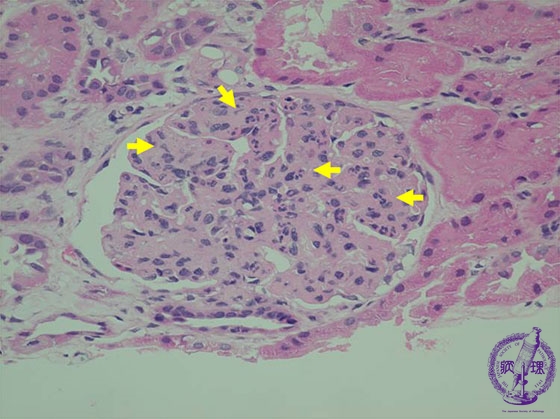

- (8)Endocapillary proliferative glomerulonephritis

Microscopic findings (HE, high power): There is an endocapillary cellular proliferation which includes neutrophils and macrophages (hypercellularity, yellow arrows).